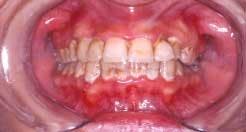

Acute necrotizing ulcerating gingivitis (ANUG) has also been shown to be clearly correlated to smoking, but no cause-and-effect relationship has been demonstrated.14 It is thought that both smoking and ANUG may be the result of underlying anxiety and stress. The condition involves primarily the free gingival margin, the crest of the gingiva, and the interdental papillae. Rarely, the lesions can spread to the soft palate and tonsillar areas, resulting in the condition known as Vincent's angina. ANUG is characterized by punched-out papilla, pronounced gingival erythema, and spontaneous hemorrhage (See Figure 2). Local lymphadenopathy and slight elevation of temperature may also be present. The disease may resolve spontaneously, but treatment usually consists of mechanical debridement and systemic antibiotic treatment.